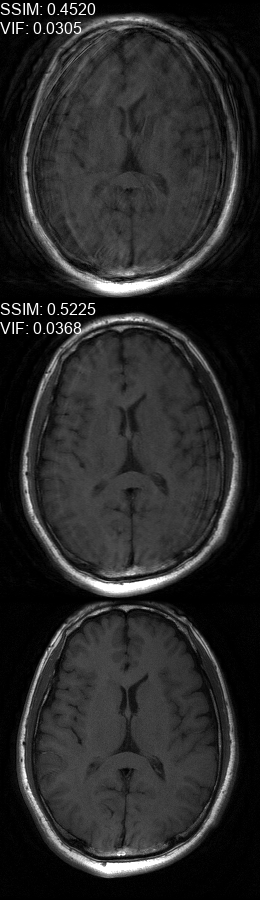

Results  Experimental results using the two presented datasets, for the fully-sampled and under-sampled k𝑘k-space scan orders, are shown in Table 1. The table presents the Normalized Mean Square Error (NMSE) obtained for each of the scan orders. For the Transaxial dataset, we only show the results for the challenging task where the DP contains only up to 707070 columns of k𝑘k-space data. All methods are able to reduce the NMSE of the corrupted scans, however the methods that incorporate the DC layer achieve a much better result. These results match our subjective visual impression of the motion-corrected images, as may be seen in Fig. 3 for simulated motion in a fully-sampled k𝑘k-space data, and Fig. 4 for an under-sampled k𝑘k-space data.

Refer to caption

(a)

(b)

(c)

(d)

(e)

(f)

Figure 3: Motion corrected images from the Diverse dataset calculated using the 𝒮260subscript𝒮260\mathcal{FS}_{260} scan order presented in Fig. 1b. The bottom row shows the motion-free image. The top row shows the motion-corrupted images. The middle row shows the corrected images calculated using our method. (a) contains a motion at t1=87subscript𝑡187t_{1}=87, (b) contains two motions at t1=46subscript𝑡146t_{1}\!=\!46, t2=170subscript𝑡2170t_{2}\!=\!170, (c) contains three motions at t1=72subscript𝑡172t_{1}\!=\!72, t2=227subscript𝑡2227t_{2}\!=\!227, t3=248subscript𝑡3248t_{3}\!=\!248, (d) contains two motions at t1=112subscript𝑡1112t_{1}\!=\!112, t2=216subscript𝑡2216t_{2}\!=\!216, (e) contains a motion at t1=66subscript𝑡166t_{1}\!=\!66, (f) contains three motions at t1=65subscript𝑡165t_{1}=65, t2=135subscript𝑡2135t_{2}\!=\!135, t3=159subscript𝑡3159t_{3}\!=\!159.